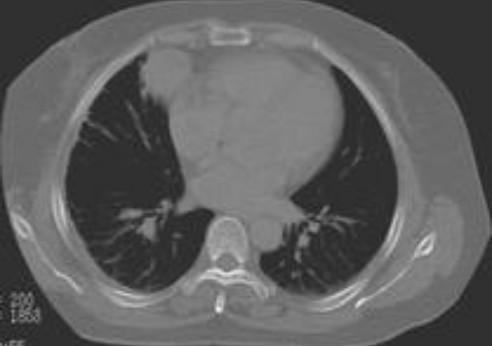

春节前夕吴小姐肚子很痛,到深圳怡康产医院用四维彩超检查发现,右侧附件中有混合回声区,并可触摸到排球大小的包块。手术中,该院妇产专家发现,吴小姐长了一个畸胎瘤,且有一定年数,而从畸胎瘤中拿出的东西令人不寒而栗:骨骼、头皮、脂肪及几绺头发和25颗成人牙齿。